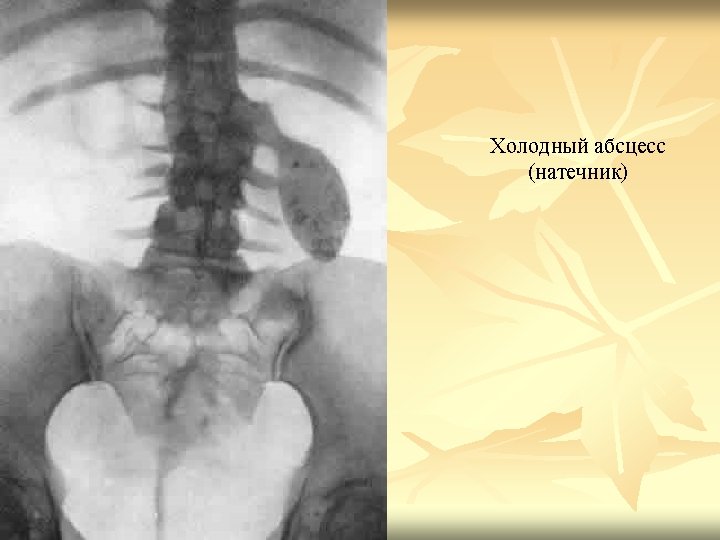

Causes n n n Hernia; Muscle diastasis; Eventration; Groin lymphadenitis; lipoma, atheroma, neurofibroma; adenophlegmon; Lymph nodes tuberculosis; metastasis; Cold abscess; Varicose diseases; Abdominal wall haematoma.